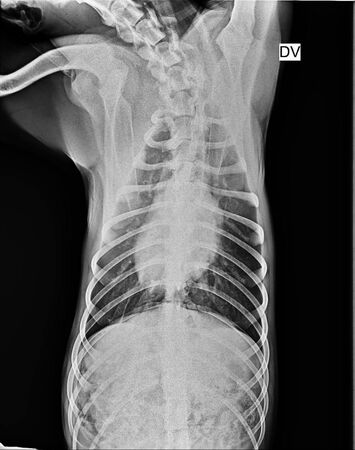

▲X光檢查後,黑狗並無骨折。(圖/翻攝自江河樹臉書)

據了解,飼主表示黑狗會咬人,當晚返家時遭咬傷,才會一時氣憤動手。目前黑狗已在動物醫院安置,初步檢查發現眼睛有外傷,但並無明顯骨折情形。